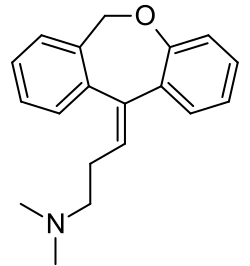

| Formula | C19H21NO |

| Molar mass | 279.383 g·mol−1 |

Chemistry

Doxepin is a tricyclic compound, specifically a dibenzoxepin, and possesses three rings fused together with a side chain attached in its chemical structure.[48] It is the only TCA with a dibenzoxepin ring system to have been marketed.[72] Doxepin is a tertiary amine TCA, with its side chain-demethylated metabolite nordoxepin being a secondary amine.[50][51] Other tertiary amine TCAs include amitriptyline, imipramine, clomipramine, dosulepin (dothiepin), and trimipramine.[73][74] Doxepin is a mixture of (E) and (Z) stereoisomers (the latter being known as cidoxepin or cis-doxepin) and is used commercially in a ratio of approximately 85:15.[2][75] The chemical name of doxepin is (E/Z)-3-(dibenzo[b,e]oxepin-11(6H)-ylidene)-N,N-dimethylpropan-1-amine[48][76] and its free base form has a chemical formula of C19H21NO with a molecular weight of 279.376 g/mol.[76] The drug is used commercially almost exclusively as the hydrochloride salt; the free base has been used rarely.[2][77] The CAS Registry Number of the free base is 1668-19-5 and of the hydrochloride is 1229-29-4.[2][77]